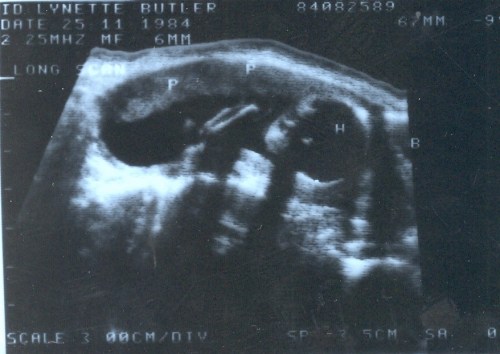

On November 25, 1984 we got our first look at the newest member of the family, but with ultrasound technology being what it was at that time and in that country, that look wasn’t a very good one.  The doctor told me that if he had to make a guess about the sex of the baby, he’d say it looked like it was a boy.  But he cautioned me against buying a lot of boy things, because it was too early (26 weeks) to be very sure

Can you even tell this is a baby?  His head is on the right side of the image.

Can you even tell this is a baby? His head is on the right side of the image - identified by the "H".